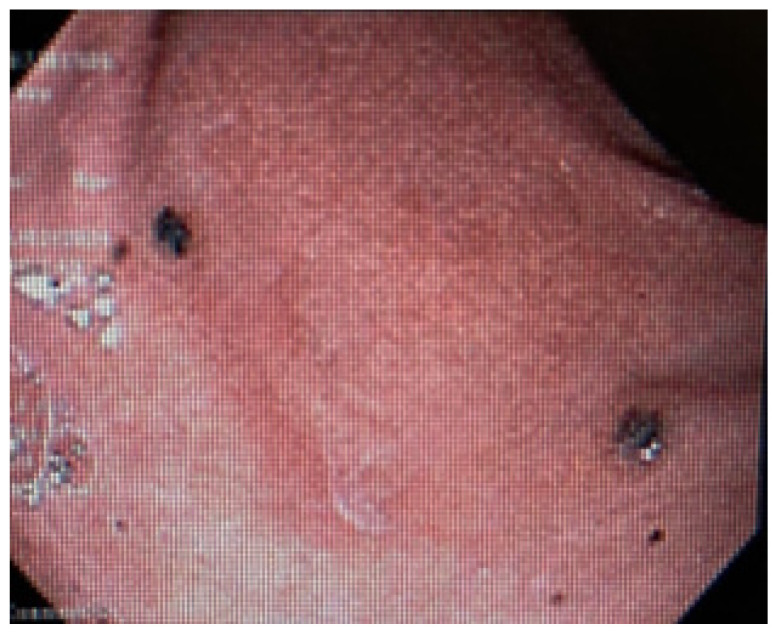

Disseminated Melanoma with Extensive Gastrointestinal Tract Involvement: Incidental Detection of Metastases on Upper Endoscopy.